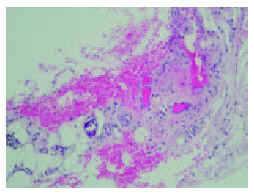

Fig. 3.--Imagen histológica de la lesión necrótica de la zona pretibial derecha. (Hematoxilina-eosina, x60.)

En la biopsia de la lesión pretibial se observó una epidermis normal, con focos de hiperqueratosis paraqueratósica; en dermis superficial y profunda se apreciaba un intenso infiltrado inflamatorio de predominio neutrofílico y una extensa zona de extravasación hemática. En el límite dermohipodérmico se advertía un vaso de mediano tamaño con la luz parcialmente ocupada por un depósito intensamente basófilo (fig. 3), cuya naturaleza cálcica se confirmó por medio de la tinción de Von Kossa (fig. 4).